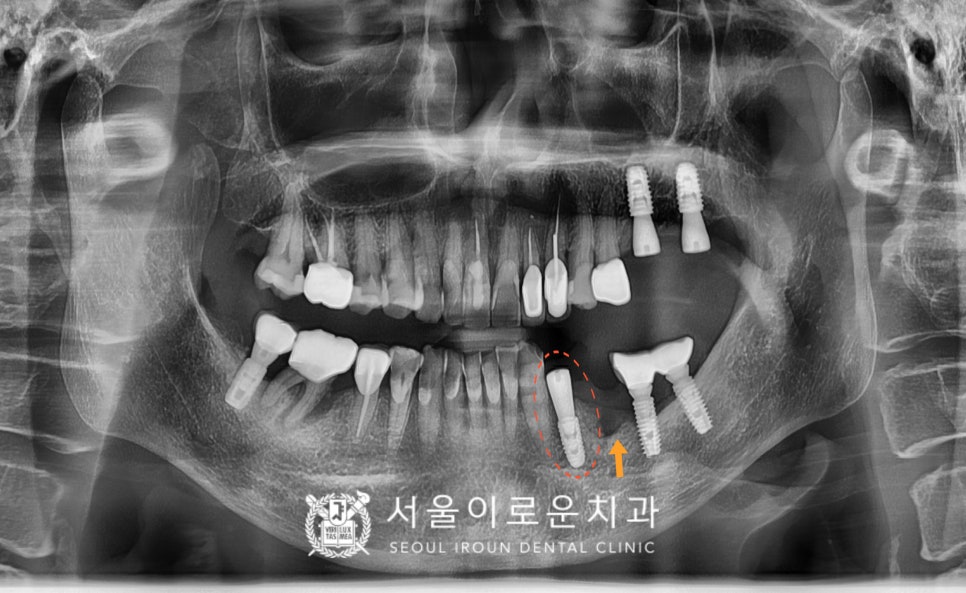

환.자분 구강 내 상황에 맞는

맞춤형 지대주인

custom abutment를 체결하여

자연치아와 강도가 가장 유사하고

심미적인 지르코니아 크라운으로

임플란트 보철을 마무리해 드렸습니다.

뼈이식을 병행한

임플란트 치료를

모두 마무리 한 구강 내 모습입니다.

환.자분께서는 이전에 흔들리고

씹.을 때 아팠던 상태가 사라져서

만.족해 하셨으며

아래턱 오른쪽 어금니 부위의 치료를

앞두고 있습니다.

✅ 전 > 후 ✅

(2024.01.26ㅡ>2024.07.29)